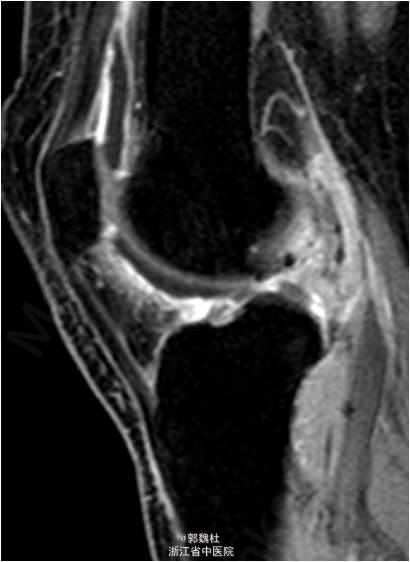

患者女,48岁,因“左膝关节色素绒毛结节性滑膜炎术后1年余”入院。患者1年前因色素绒毛结节性滑膜炎在我院行关节腔清理术,现术后1年,患者左膝关节出现肿痛,于外院行MRI检查提示色素绒毛结节性滑膜炎复发。现患者为求进一步诊治前来我院就诊,余未见明显异常。

诊断:左膝关节色素绒毛结节性滑膜炎(PVNS)术后复发。行左膝关节镜检,关节内病灶清理术。术后开始行股四头肌肌力训练及踝泵训练,术后第3天开始主动肌力训练,术后第4天主动屈膝达90°,术后第5天可完全负重。